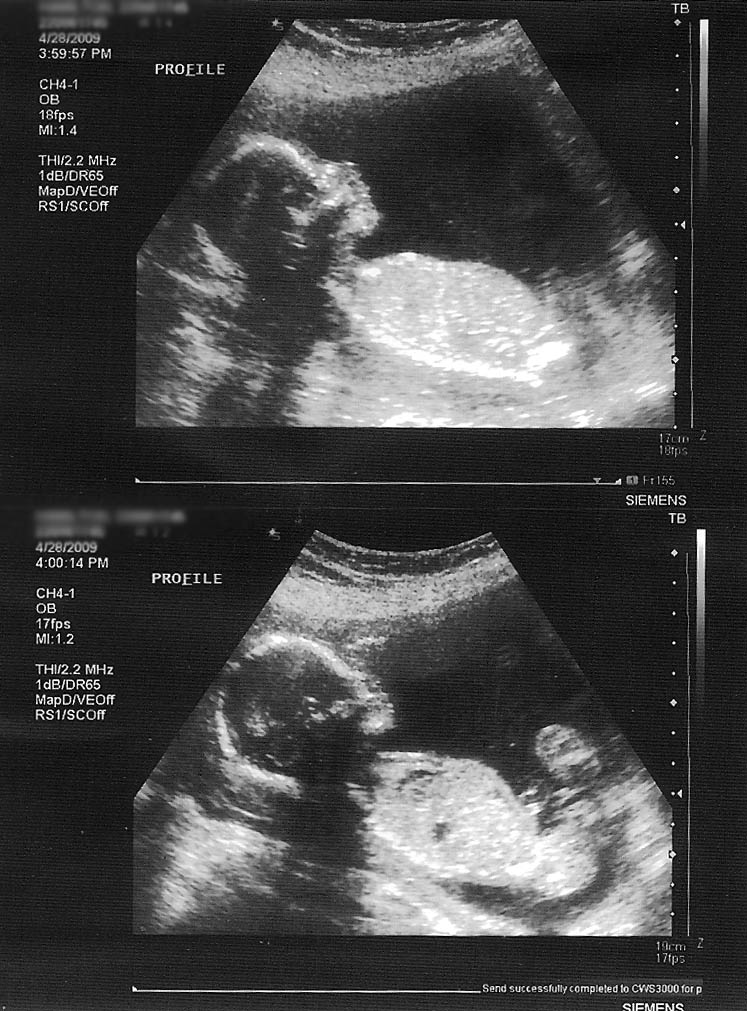

Well we just had another appointment with the doctor and got yet another ultrasound (I hope our baby doesn’t come out glowing or with three eyes from all the ultrasounds 🙂 sharon had been feeling a lot of anxiety leading up to this appointment because she had not been feeling any movement in there. I tried to reassure her by telling her we did not feel Noah kick until after 20 weeks, I know because i blogged everything. Nonetheless she was nervous. It was a great feeling to see a little baby kicking away in there. It lifted a huge weight. Now on to other important issues, such as…is that baby a girl in there?

We had been reading so much information about mis-reading ultrasounds when the tech says a girl but turns out to be a boy because it was too early to tell. Our minds were finally put to rest when we heard the words “It is for sure a girl”. Whew. If she were a he, we did have a contingency plan for a name. We were going to do Nora backwards, which would be Aron. But that will not be necessary. Now we can begin accumulating baby girl stuff and get her room ready in our new house. We had previously decided not to decorate the room until we got her home, but we think she deserves the same hoopla that Noah got.